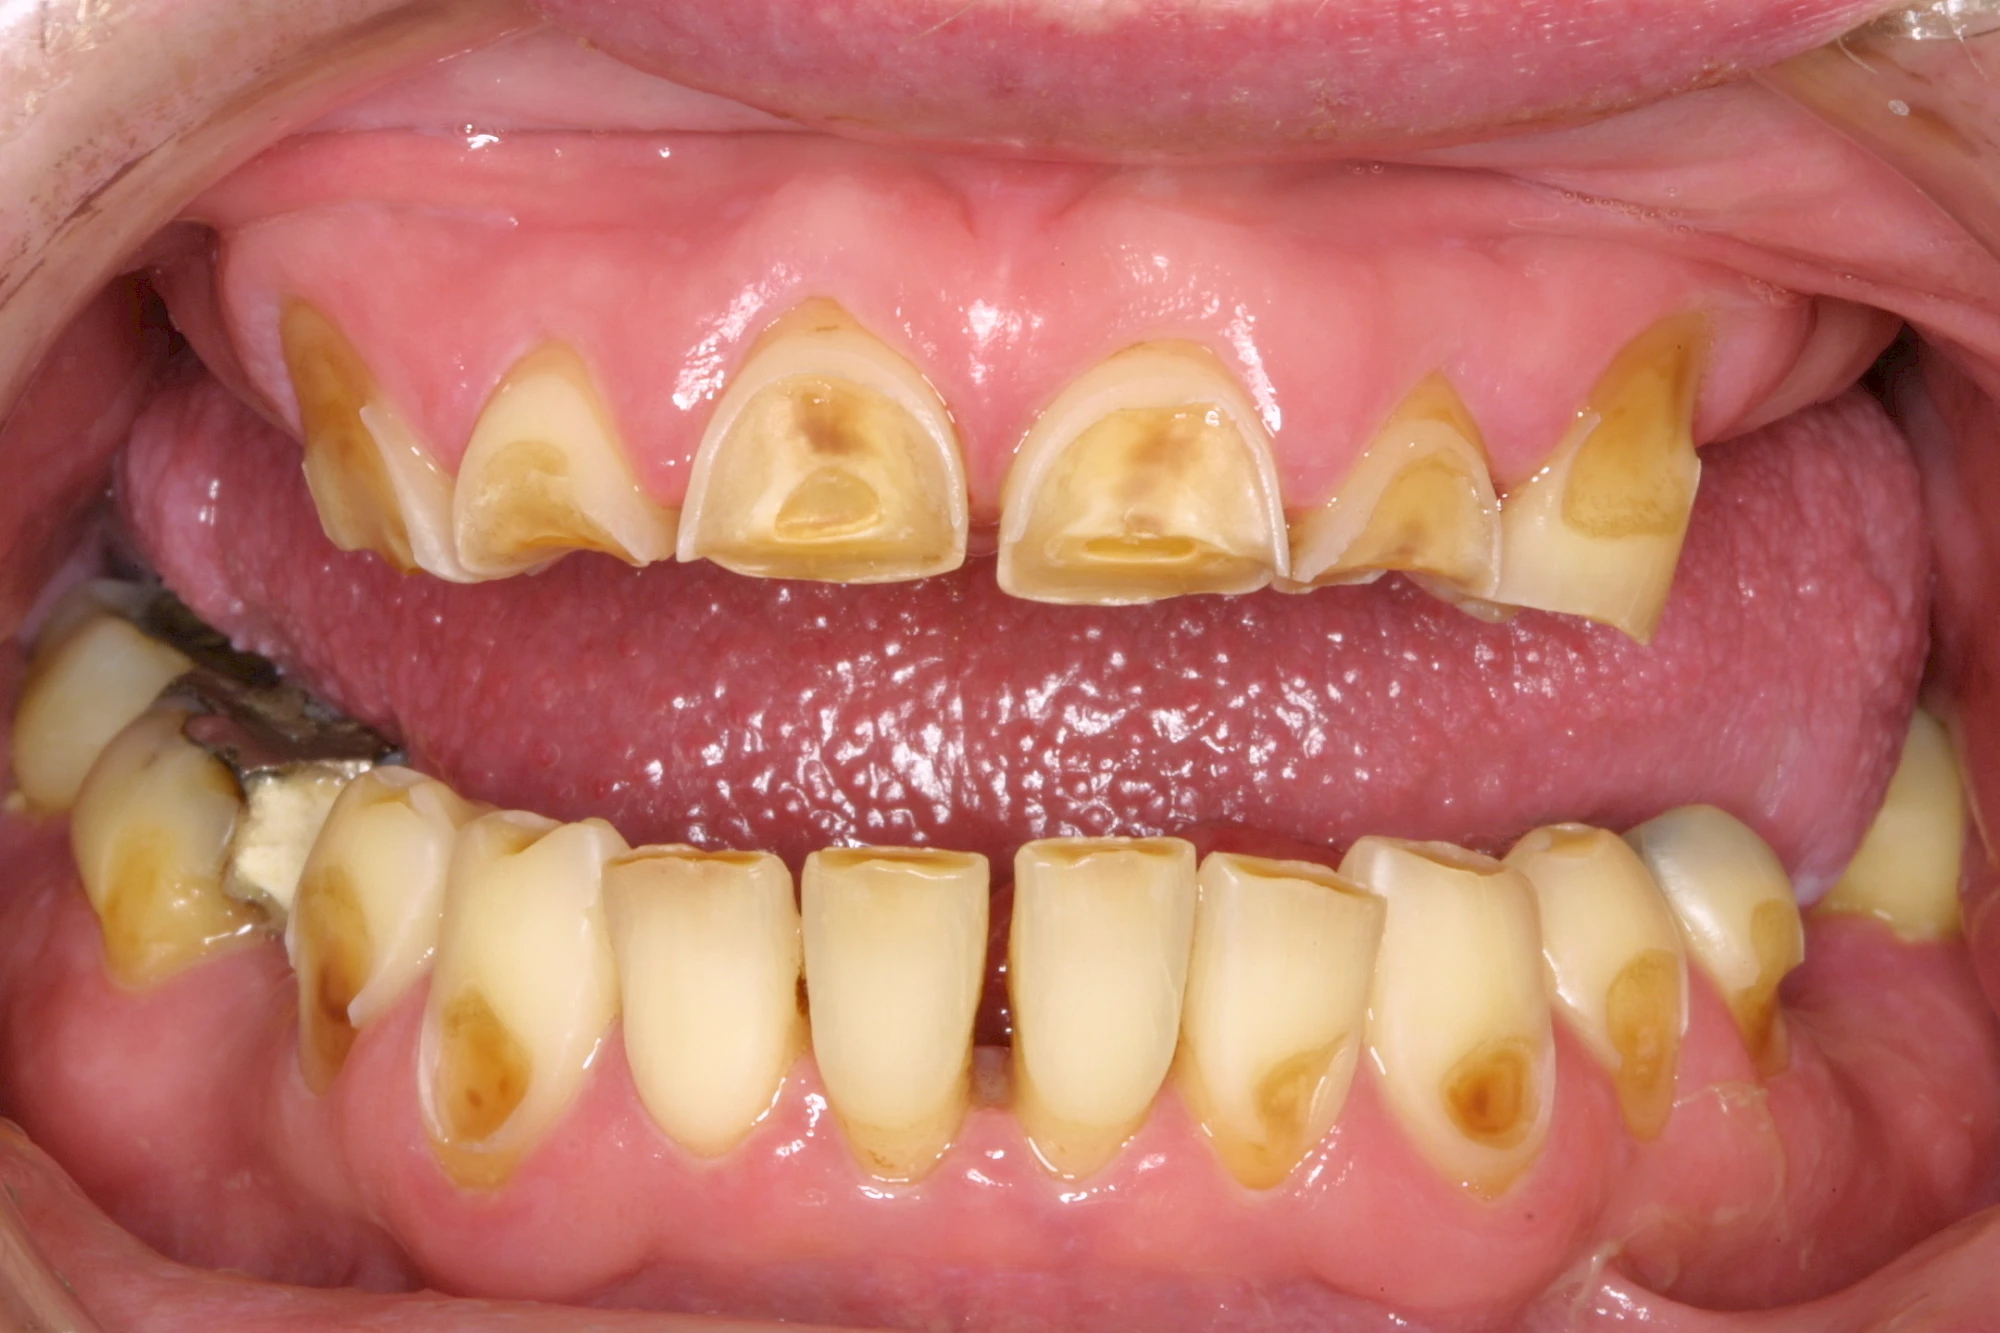

Auswaschung (Erosion) dagegen ist eine Verschleißerscheinung der Zähne aufgrund von immer wiederkehrenden Säureangriffen durch die Nahrung, verstärkt zum Beispiel durch den Genuss säurehaltiger Getränke oder Speisen. Auch bei Menschen mit einer Essstörung (z. B. Bulimie) können die Zähne durch die Magensäure ausgewaschen erscheinen.